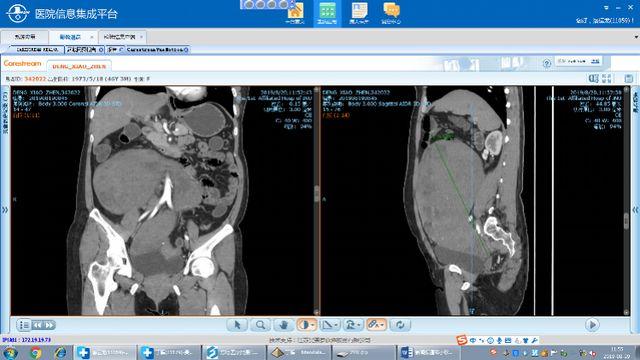

用最短时间内为患者复查了盆腹腔彩超,完善了血常规、凝血功能,心电图、全腹CT、胃肠镜等术前必备检查。检查结果果然发现了端倪,盆腹腔见一巨大不均质回声团,上界达剑突下,双侧至腋前线,前后径约101mm,其内可见条状血流信号。

腹部CT检查更是发现,患者的腹、盆腔巨大肿块影,最大层面大小约25*13*22cm,周围肠管受推压,肿块内可见迂曲的子宫动脉,肿块下段与子宫分界不清。